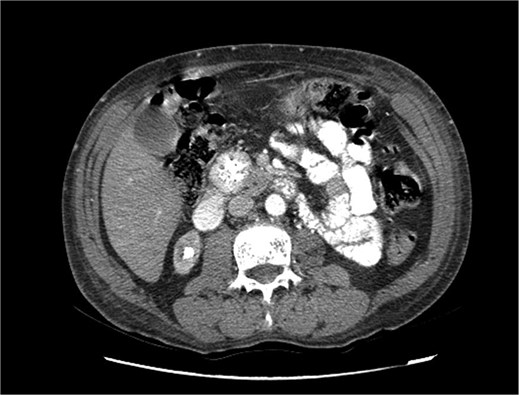

Upon admission in January 2025, the patient presented with altered mental status, dehydration, and hypoglycemia. The recurrence of hypoglycemic episodes was confirmed by laboratory studies and imaging, which identified a well-defined 3 cm mass in the pancreatic head on triphasic computed tomography (Figs 1–3). Given the diagnosis of recurrent malignant insulinoma and the possibility of resection, a surgical approach was chosen.

Triphasic computed tomography of the pancreas, arterial phase, showing a tumor in the head of the pancreas.